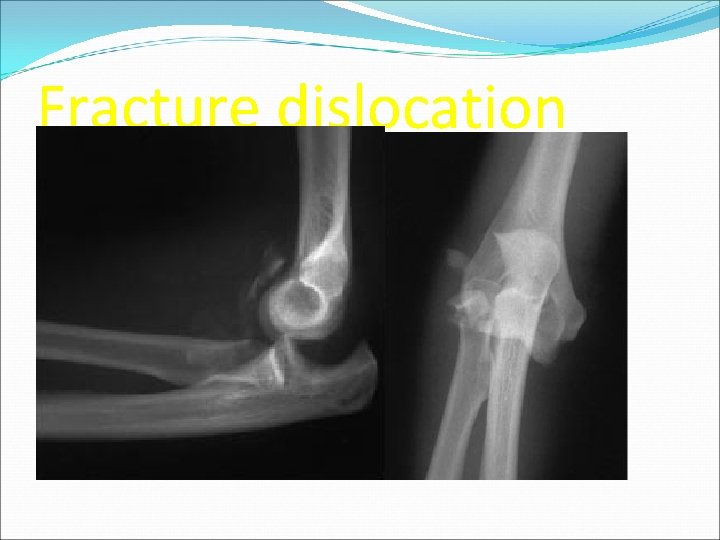

n Simple no associated fracture account for 50 -60% of elbow dislocations n complex associated fracture present may take form of terrible triad injury involves a disruption of the LUCL, a radial head fracture, a coronoid tip fracture and a dislocation of the elbow

Fracture dislocation

complications n Varus Posteromedial instability n Loss of motion n Neurovascular injuries (ulnar/median nerves) n Compartment syndrome n Damage to articular surface n Chronic instability n Heterotopic ossification n Contracture/stiffness correlated with immobilization beyond 3 weeks